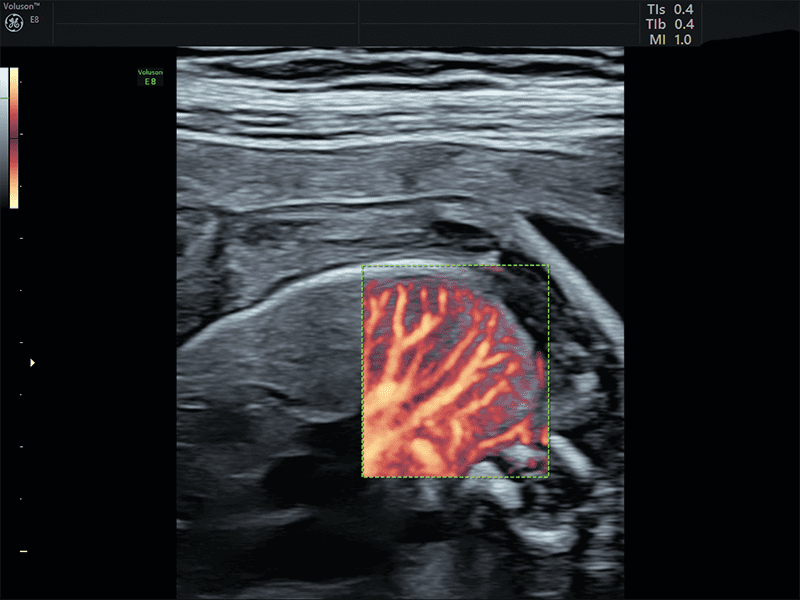

Radiantflow: algoritmo avanzato che permette di ottenere informazione di altezza e profondità del Color Doppler, Power Doppler e HDFlow™ con visualizzazione in tempo reale 3D Like.

SlowflowHD™: software per lo studio della vascolarizzazione che grazie all’altissima sensibilità è in grado di sopprimere i movimenti a bassa frequenza preservando le informazioni sul flusso.

Slowflow 3D: È possibile abbinare le varie tecnologie Volume Ultrasound integrate nella piattaforma per uno studio approfondito delle strutture vascolari del cervello fetale, dei vasi addominali e in applicazioni ginecologiche, quali lo studio dell’adenomiosi tramite Slowflow 3D.